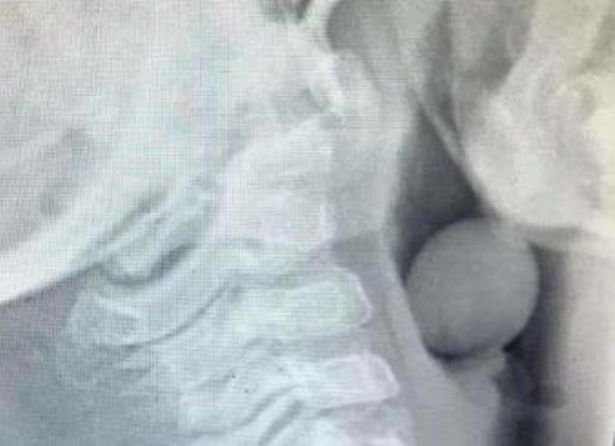

小孩子吃東西噎到非常危險,所以醫生都建議家長如果可以的話,一定要把食物切一下再給小孩吃,不然不小心吞下去可是會有生命危險的!近日一名澳洲的部落客Angela Henderson就分享了一張照片,裡面是一名5歲小孩的X光照片,可以看到一顆葡萄就這樣卡在小孩的喉嚨裡。Angela說:「大家請注意,有些小孩還不會每次都嚼食物,尤其是在玩的時候。請小心這樣的狀況,不要因為只是葡萄、小番茄就覺得很安全喔!」

小孩子的呼吸道差不多就是葡萄的寬度,所以很多爸媽都不知道其實葡萄、小番茄都應該要先切過才可以給小孩吃喔!Angela表示照這個X光的男孩後來還要動小手術,才能把葡萄拿出來。她說這孩子很幸運,因為葡萄沒有塞滿整個呼吸道,如果都塞滿的話恐怕會有生命危險,所以請大家要記得,所有的小食物像說葡萄、小番茄、蛋、巧克力糖果等等,都還是要切小塊才安全喔!